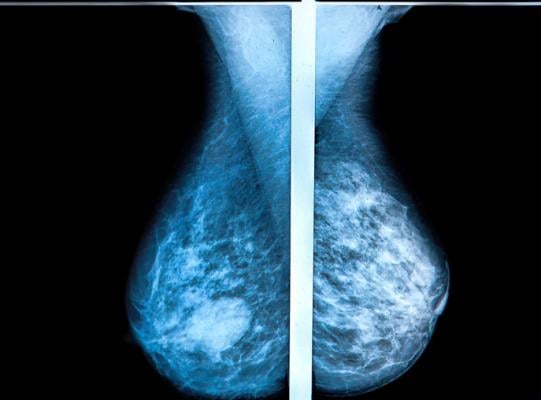

Getty Images

So it was with the introduction of three-dimensional tomosynthesis mammography, which allows radiologists and oncologists to see deeper into breast tissues by taking multiple images and allowing specialists to interpret each layer almost as if they were reading a book.

The technology promised greater efficiency at cancer detection and fewer callbacks on patients for whom the interpretation of results was unclear or uncertain.